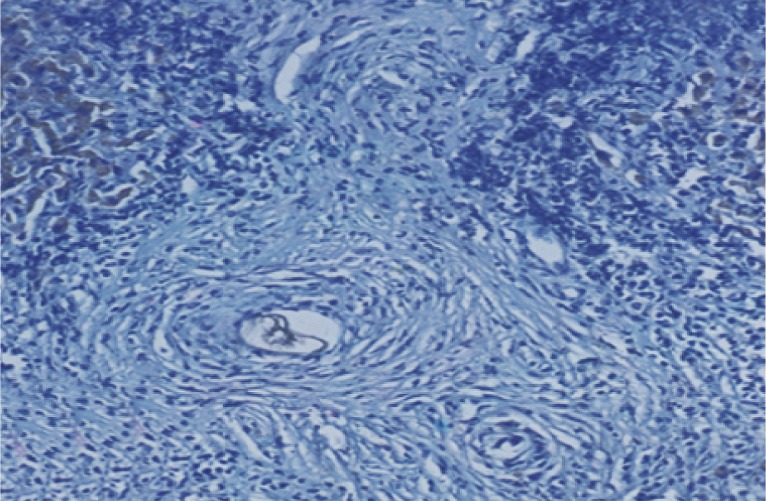

The mean granuloma count in the treated groups with BMSCs and BMSCs-HGF revealed a marked reduction accompanied by an obvious reduction in the mean granuloma number and diameter (Table 1; Figs. 2, 3).

Morphometric studies using Sirius red staining showed significant decreases in the fibrous tissue in BMSCs and BMSCs-HGF-treated groups compared to the infected control group (Figs. 6,7,8,9,10,11,12,13,14,15).

After treatment with BMSCs alone or in combination with HGF, there was an improvement in the histopathological picture of the liver which included diminution in the number and diameter of granulomas and reduction in the fibrotic content. Similar to the present findings, Abdel Aziz et al. [13] focused on the antifibrotic effect of mesenchymal stem cells (MSCs) on the liver of S. mansoni-infected mice. In their model, once granulomas were formed around the S. mansoni ova, the rate of spontaneous change of the collagen content of the granuloma was low, thereby providing a relatively stable in vivo model for analyzing collagen turnover. The histopathological examination of the liver of the S. mansoni-infected mice showed characteristic granulomas, which were cellular and contained thick collagen bands. After MSCs infusion, the granulomas decreased in size and number and became less cellular, although the concentric fibrous bands were still discernible.